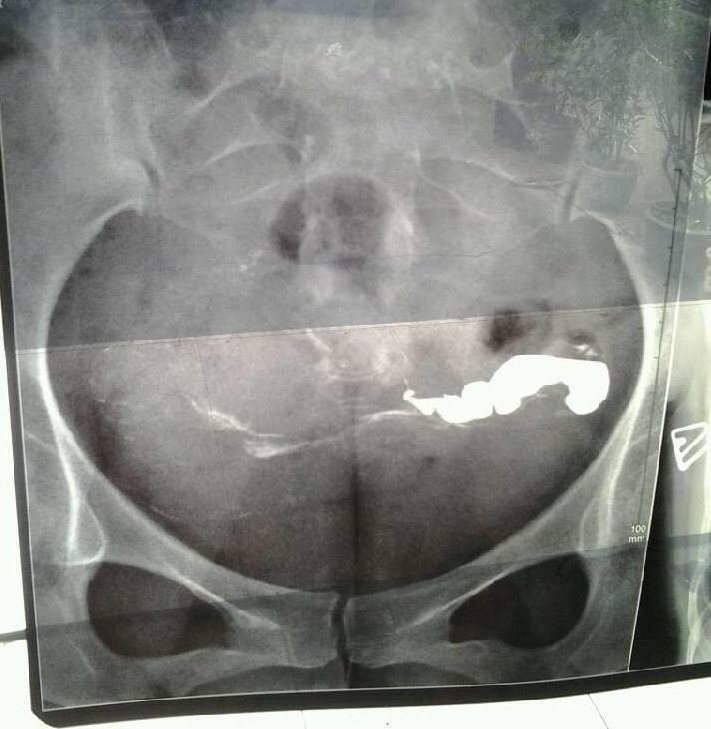

求讲解输卵管造影图片

我做的碘油造影,医生说让我做腹腔镜。我考虑到会留疤痕之类的,我输卵管这种情况是不是必须做腹腔镜啊?是不是真的全部堵上了??第二张是第二天重拍的。